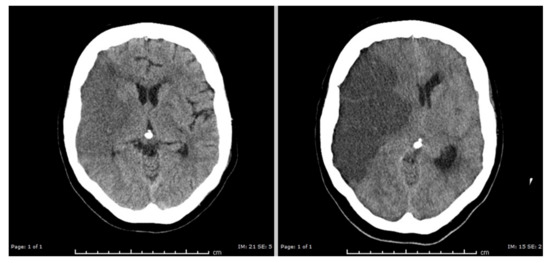

- Dostovic, Z.; Dostovic, E.; Smajlovic, D.; Avdic, L.; Ibrahimagic, O.C. Brain Edema After Ischaemic Stroke. Med. Arch. 2016, 70, 339–341. [Google Scholar] [CrossRef]